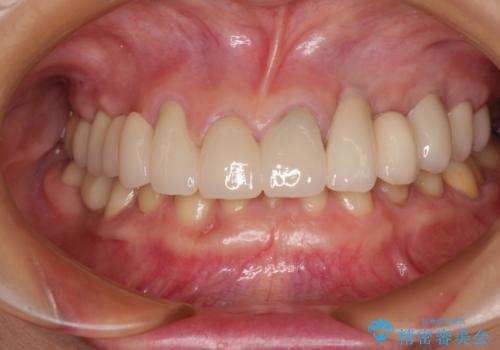

インビザライン・ライトは、製作できるアライナーの枚数に制限があるため、移動可能な量に限りがあります。

一方で、半年から1年程度で治療を終えることができるため、軽度の歯列不正の患者様には大変お勧めです。